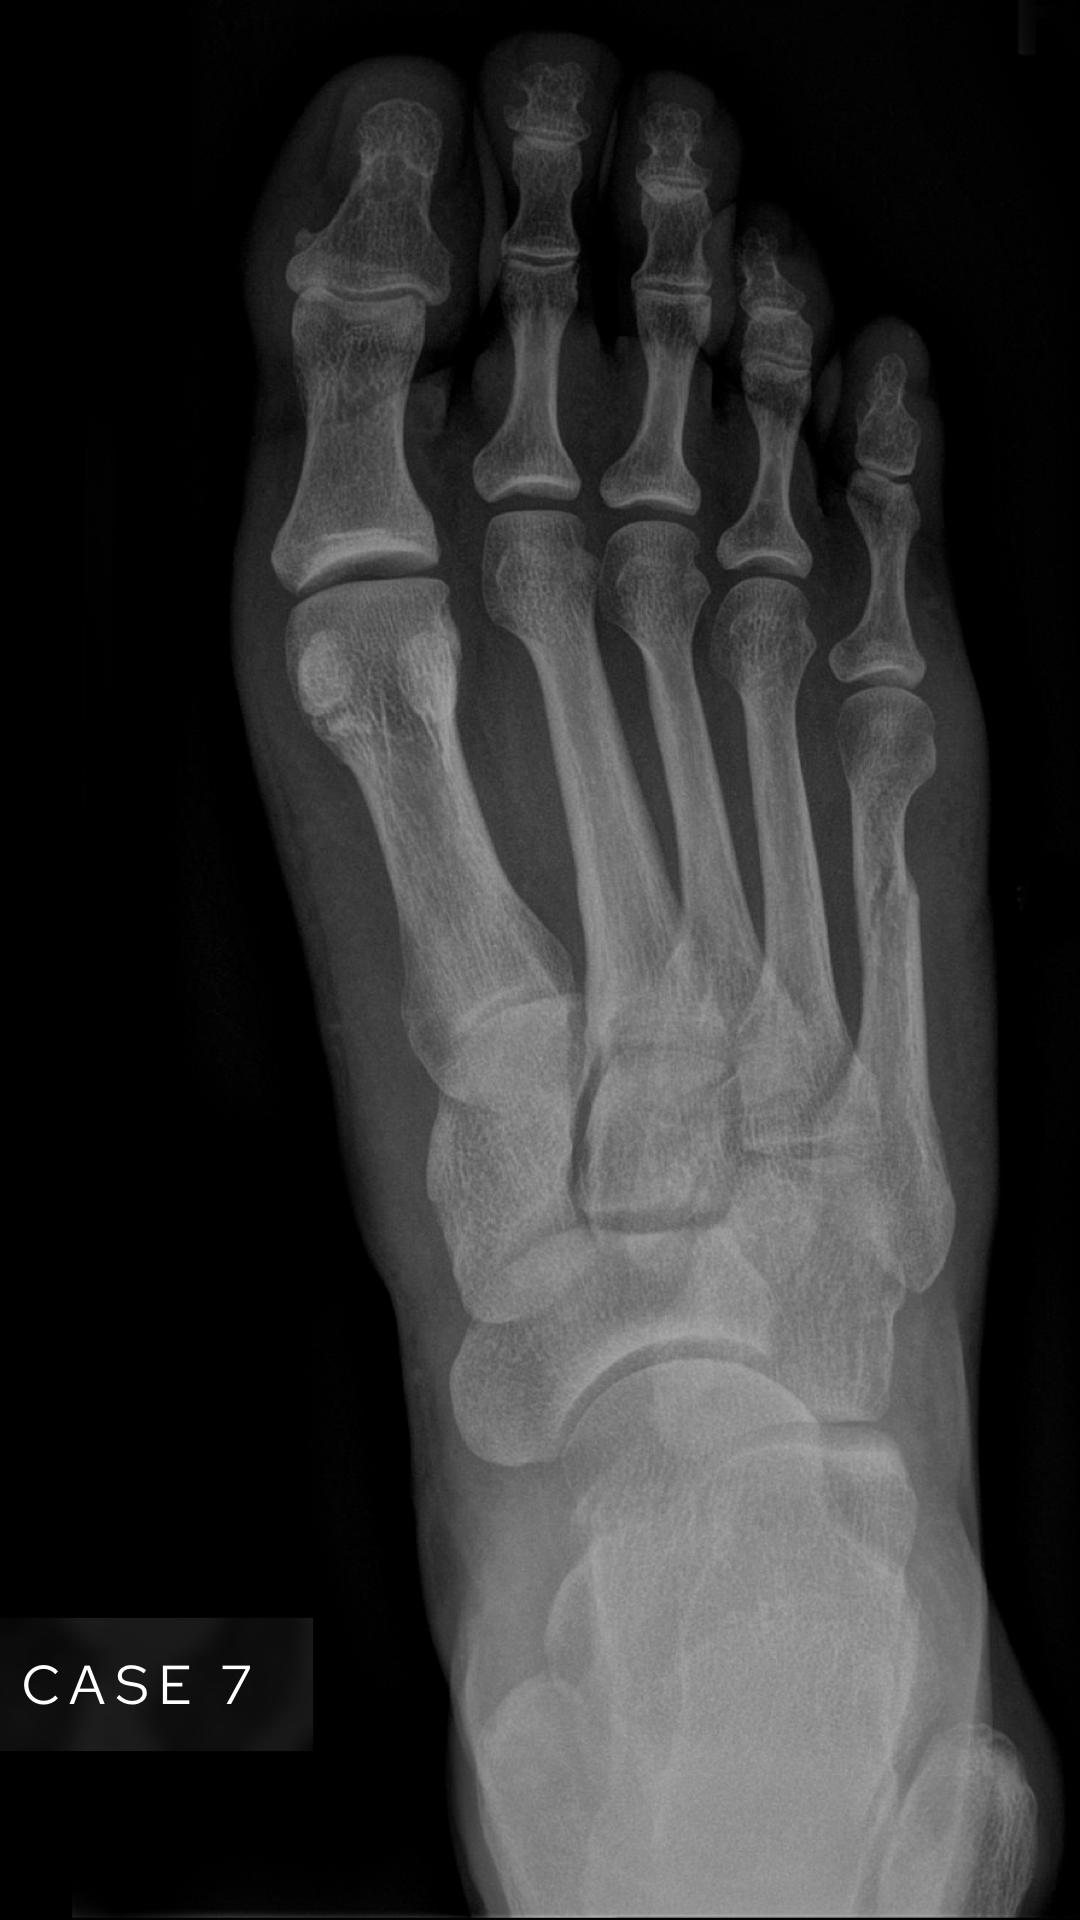

Case 7

A female in her 40s presents to the ED with foot pain after an episode of trauma. What does the foot X-Ray show?

Choose from one of the following: